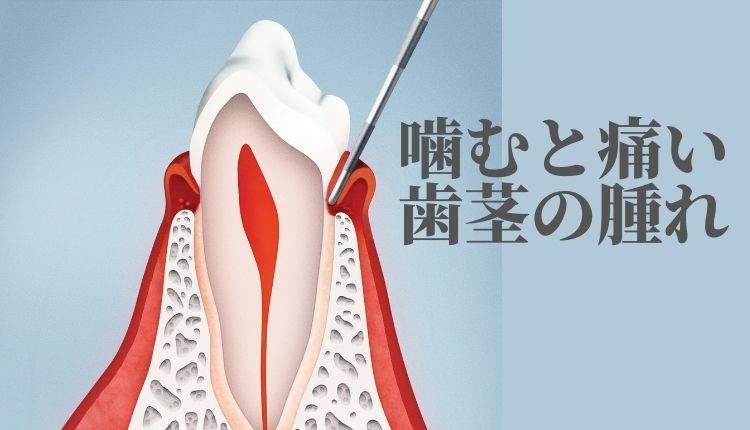

おっしゃる通り歯周病は歯肉が腫れてきますし

膿もたまります。

おっしゃる通り歯周病は歯肉が腫れてきますし

膿もたまります。

□ 歯肉がむずがゆい、痛い。

□ 歯肉が赤く腫れている。(健康的な歯肉はピンク色で引き締まっている)